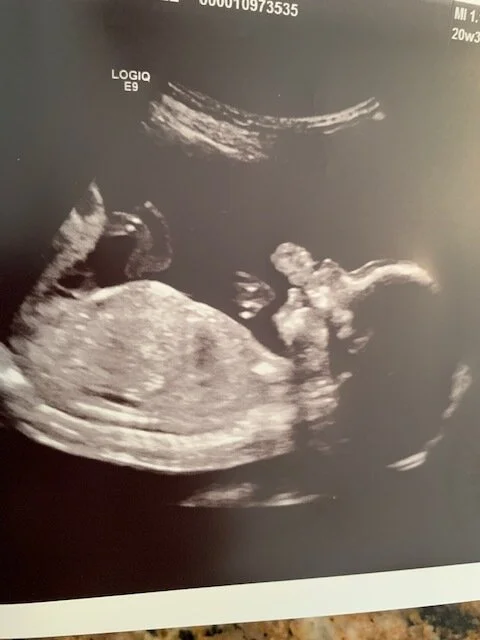

Today we learned that this little life inside me is a boy. I wasn’t surprised. I had a feeling from very early on that this baby was a boy, but there’s still such excitement to see that reality on the ultrasound screen. Within seconds of the ultrasound starting Kraig looked at the screen and said, “It’s a boy!” Baby BOY was in the perfect position to give us that news at the beginning of the scan. For the next 45 minutes we watched in awe as our boy hiccuped, sucked his hand, wiggled, and flipped. Being able to see this tiny life so alive within me absolutely amazes me every time.